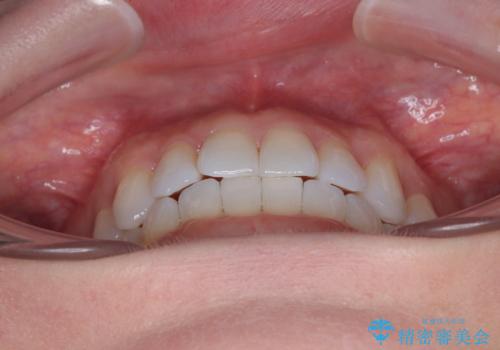

前歯のデコボコをインビザラインで綺麗に

- 上下前歯の叢生を気にして来院された患者様です。

インビザラインでの治療を希望されていて、デコボコの程度が中等度であり、安価なパッケージにて対応可能と判断されたため、インビザライン・モデレートを用いて矯正治療を行うこととしました。